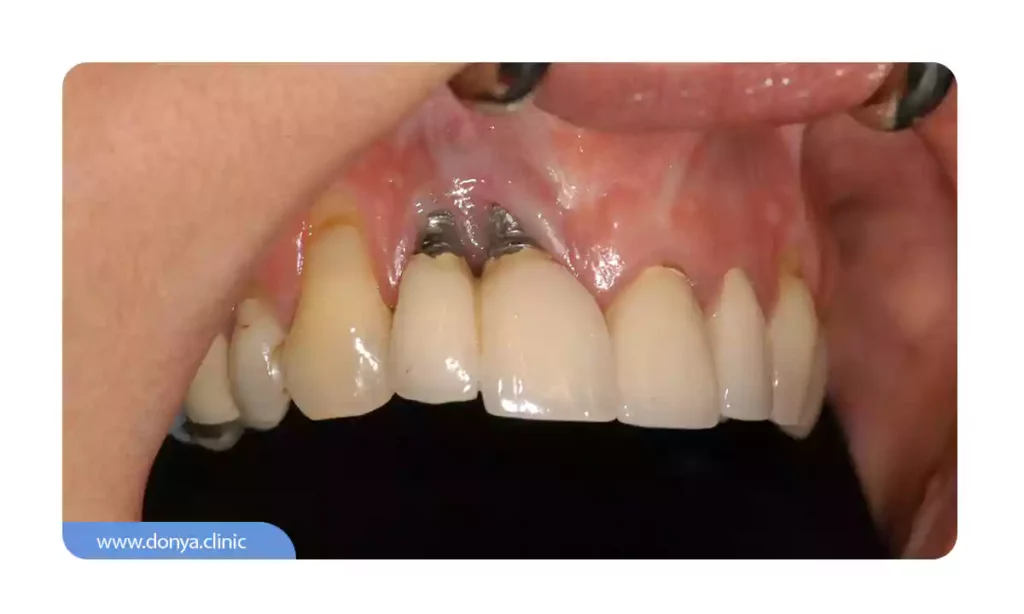

1. شکستن ایمپلنت

شکست درمان تا زمانی که رخ ندهد نمی تواند جزء عوارض ایمپلنت دندان باشد با این حال اگر به هر دلیلی نتیجه درمان آنطور که پیش بینی می شود حاصل نشود، عوارض زیادی رخ خواهد داد. در موارد نادر، ایمپلنت ممکن است به درخونستی با استخوان فک ادغام نشود که این مساله می تواند باعث لق شدن ایمپلنت یا حتی افتادن آن شود. این اتفاق ممکن است به دلایل مختلفی از جمله موارد زیر رخ دهد:

- ناکافی بودن تراکم استخوان

- عفونت

- وارد شدن ضربه به صورت

- بارگزاری پروتز غیراستاندارد قبل از جوش خوردن ایمپلنت به فک

- کاشت ایمپلنت ضعیف

شایان ذکر است که ایمپلنت های دندانی دارای میزان موفقیت بسیار بالایی هستند و در برخی مطالعات میزان موفقیت آن تا 98 درصد گزارش شده است. با این حال، موفقیت ایمپلنت به عوامل مختلفی از جمله سلامت کلی بیمار، عادات بهداشت دهان و دندان و مهارت و تجربه دندانپزشک یا جراح دهان که این عمل را انجام می دهد بستگی دارد.